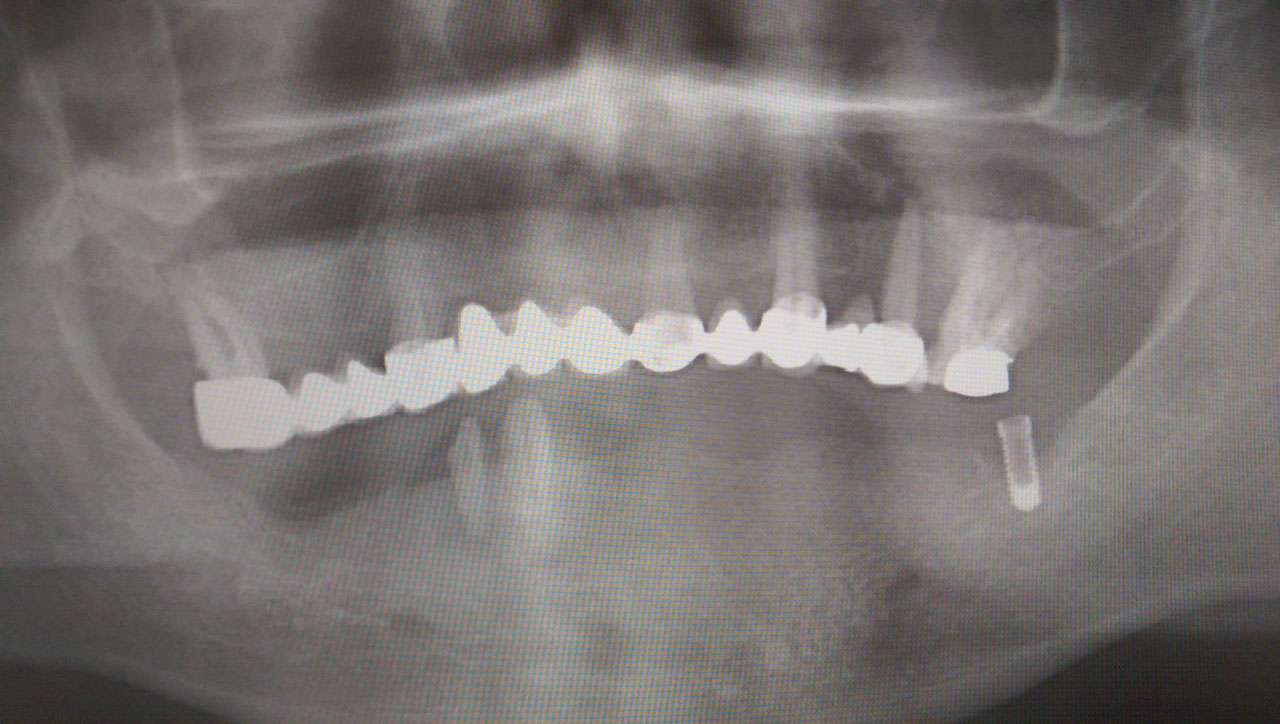

Alsó állcsont teljes rehabilitációja 72 óra alatt, azonnal terhelhető implantátumokkal súlyos paradontitisben szenvedő dohányzó páciens esetében. Az alsó állcsont fogai mind mozogtak az előrehaladott fogágypusztulás miatt.

A fogakat eltávolítottuk, a gyulladt, fertőzött csontot kitakarítottuk, kifertőtlenítettük, majd azonnal implantáltunk.

Svájci, IHDE márkájú, azonnal terhelhető implantátumokat helyzetünk be, és ezekre harmadnapra rögzített, hosszútávú, fémvázas, esztétikus műanyaggal leplezett hidat ragasztottunk be.

Ezt az ideiglenes hidat a sebek gyógyulása miatt használjuk, de tartóssága miatt véglegesként is használható. A legtöbb esetben, ahogy itt is, 6 hónap múlva porcelán hídra cseréljük, a teljes gyógyulás után.